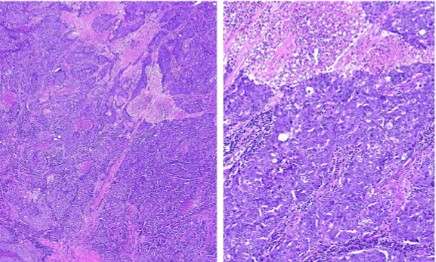

Cho đến hiện tại, không có liệu pháp nhắm trúng đích cụ thể nào được tìm thấy cho ung thư vú dạng giống đáy, tuy nhiên, một số thử nghiệm lâm sàng đã được thiết kế để tìm ra câu trả lời(23,30). Về mặt hình thái, ung thư vú dạng giống đáy được đặc trưng bởi tỉ lệ phân bào cao, tăng hoạt động tăng sinh, u thường lớn với hoại tử bản đồ trung tâm và bờ không thâm nhiễm, thấm nhập lympho bào với các đặc điểm giống như dạng đa bào (Hình 6)(2,23). Ung thư vú dạng giống đáy thường thấy ở phụ nữ trẻ người Mỹ gốc Phi và những người mang gen BRCA1 đột biến. Loại ung thư vú đặc biệt này thường diễn tiến nhanh, di căn đến phổi và não, phần lớn bệnh nhân tử vong trong vòng 5 năm đầu tiên.

Hình 5. Nhóm giống đáy. A, Mô bệnh học nhóm giống đáy. B, hoại tử và đặc điểm mô bệnh học giống dạng đa bào